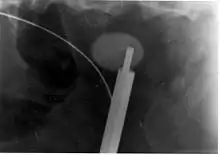

A lithotriptor machine with a mobile fluoroscopic system ("C-arm") is seen in an operating room; other equipment is seen in the background including an anesthesia machine.

Extracorporeal shock wave lithotripsy (ESWL) is a noninvasive technique for the removal of kidney stones. Most ESWL is carried out when the stone is present near the renal pelvis. ESWL involves the use of a lithotriptor machine to deliver externally applied, focused, high-intensity pulses of ultrasonic energy to cause fragmentation of a stone over a period of around 30–60 minutes. Following its introduction in the United States in February 1984, ESWL was rapidly and widely accepted as a treatment alternative for renal and ureteral stones.[106] It is currently used in the treatment of uncomplicated stones located in the kidney and upper ureter, provided the aggregate stone burden (stone size and number) is less than 20 mm (0.8 in) and the anatomy of the involved kidney is normal.[107][108]

For a stone greater than 10 millimetres (0.39 in), ESWL may not help break the stone in one treatment; instead, two or three treatments may be needed. Some 80-85% of simple renal calculi can be effectively treated with ESWL.[7] A number of factors can influence its efficacy, including chemical composition of the stone, presence of anomalous renal anatomy and the specific location of the stone within the kidney, presence of hydronephrosis, body mass index, and distance of the stone from the surface of the skin.[106]